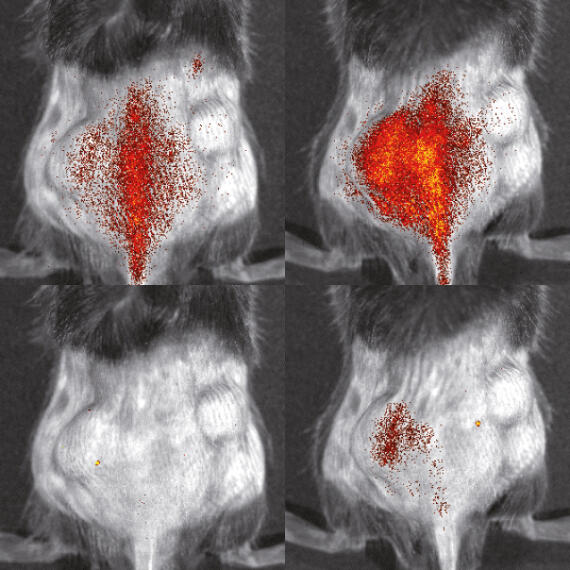

Verteilung von Immunzellen im Körper einer Maus, aufgenommen mit optischer Bildgebung

© S. Gran & L. Honold et al./Theranostics 2018(8)

In diesem Projekt entwickeln wir Methoden, mit denen Immunzellen vor, während und nach einer Immunbehandlung beobachtet werden können. Wir sehen uns die Vorgänge zunächst in Krankheitsmodellen bei Tieren an – mit dem Ziel, die Ergebnisse und Methoden zeitnah auf Patienten zu übertragen und letztendlich Immuntherapien bei Krankheiten wie Krebs oder Entzündungen „bildgesteuert“ zu verbessern.